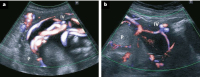

Abbildung 3: Beispiele von Vasa praevia in unterschiedlicher sonographischer Darstellung. P: Plazenta; VP: Vasa praevia.

Abbildung 5: Insertio velamentosa bei Plazenta bilobata. P: Plazenta; IV: Insertio velamentosa.